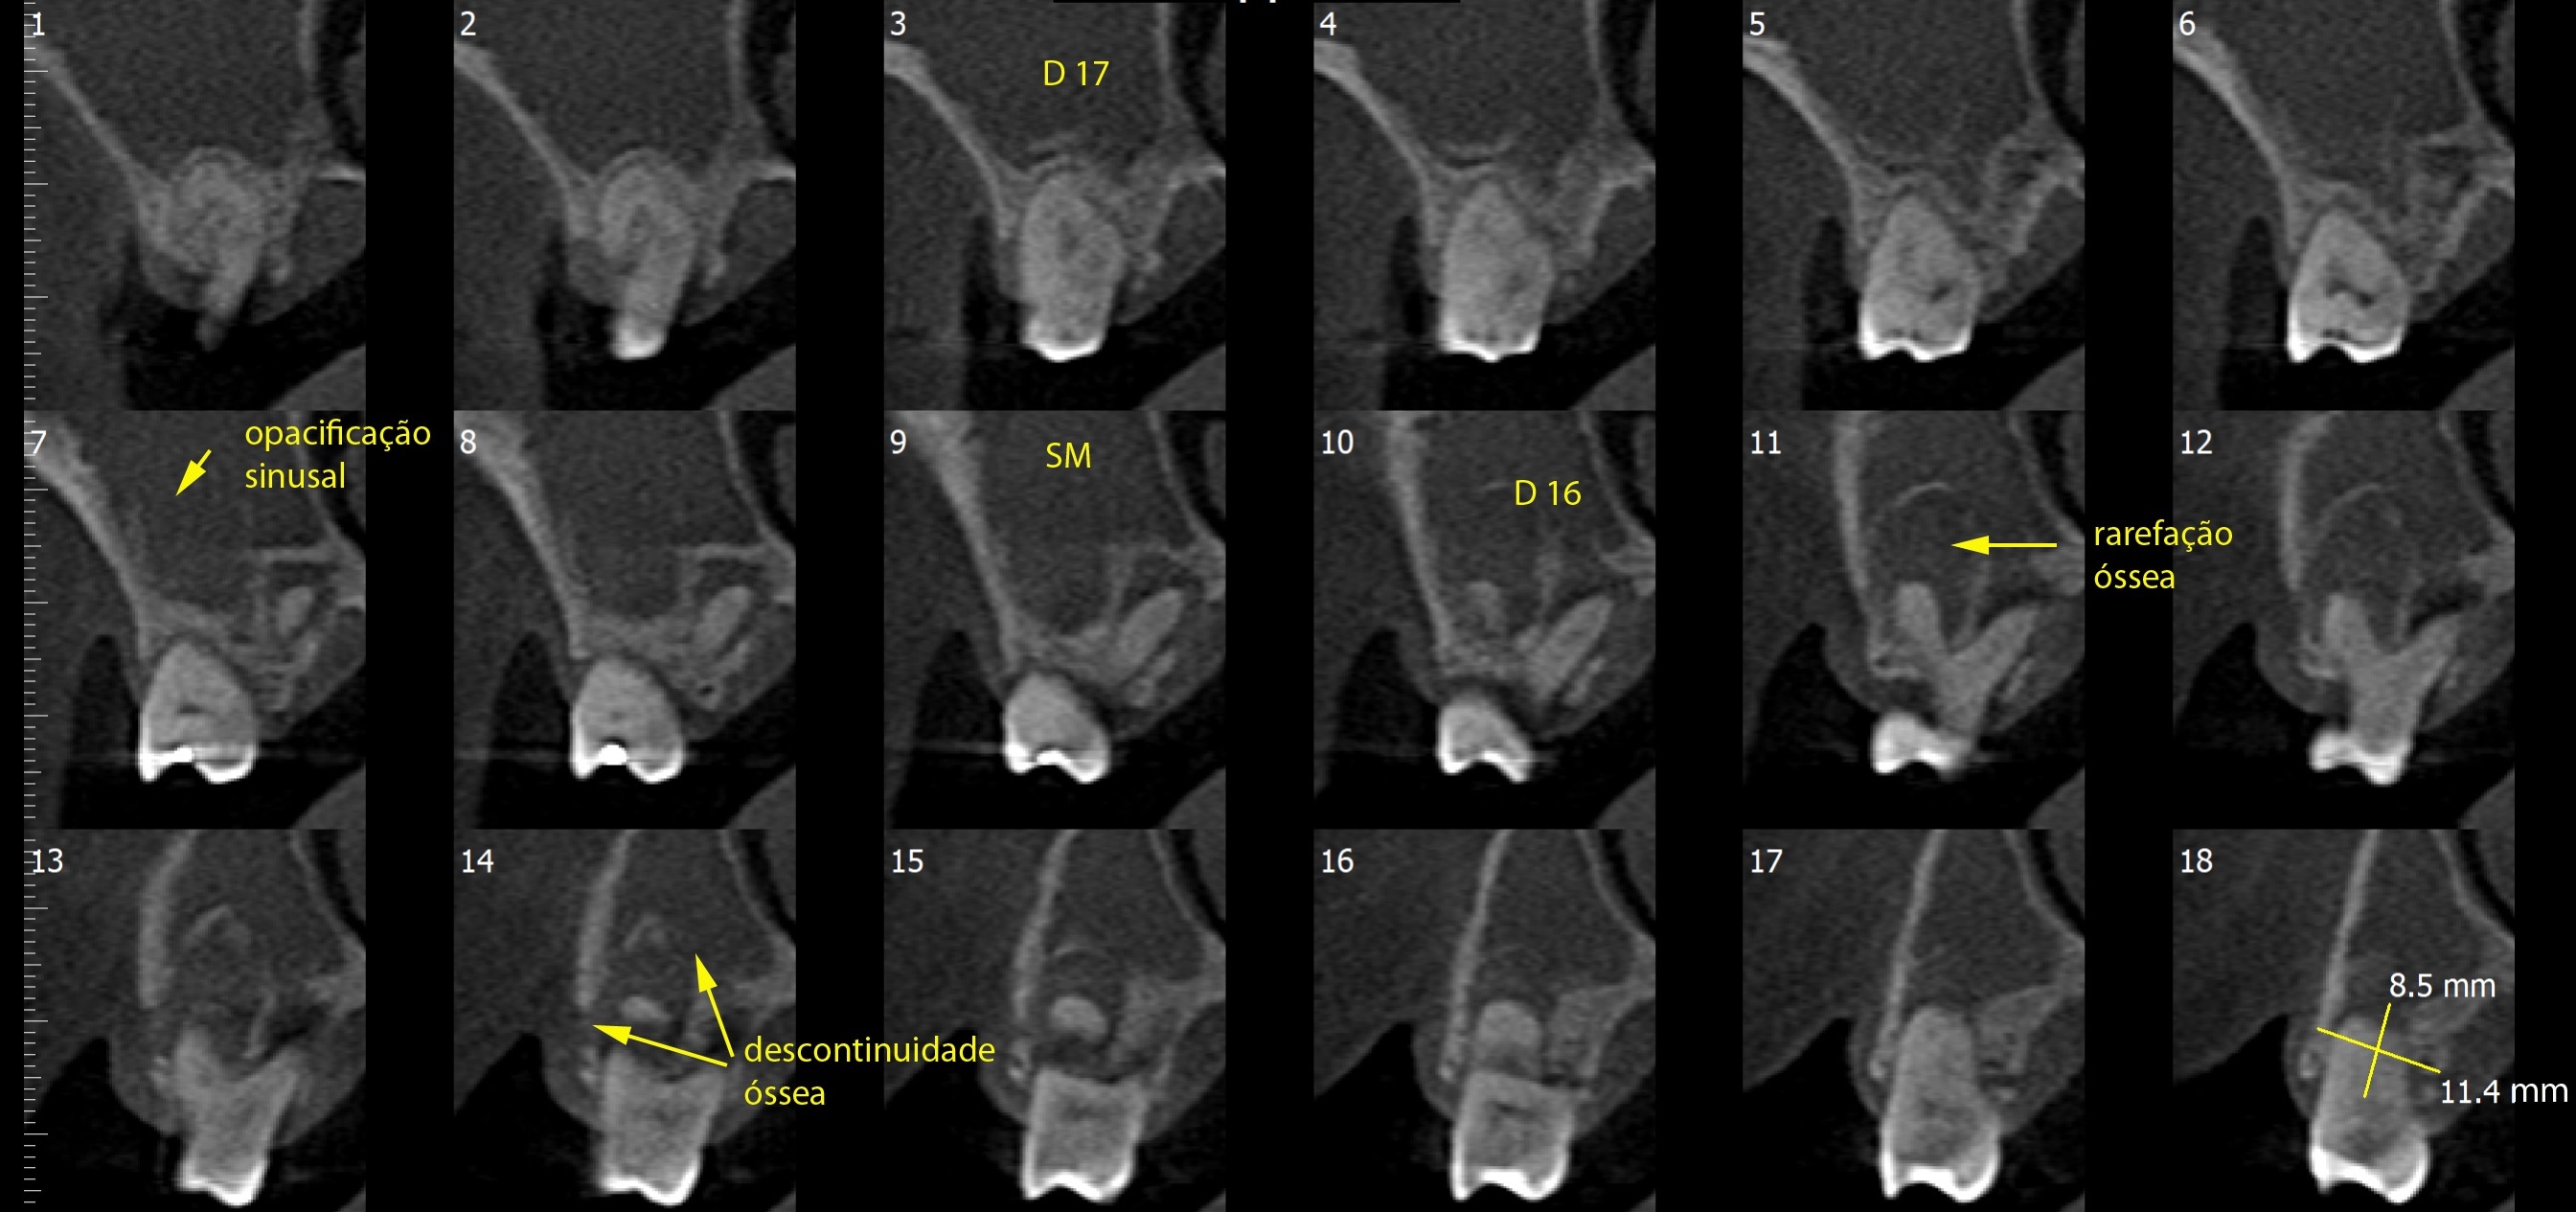

TOMOGRAFIA COMPUTADORIZADA VOLUMÉTRICA CONE BEAM

Laudos e Análises Radiográficas